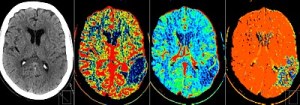

Figure 3 – CT Perfusion Study showing a Left Parietal Lobe Infarct:32

Essentially, CT Perfusion studies aim to identify areas of ischaemic brain tissue that may survive the acute phase of hypoperfusion if an adequate flow of cerebral blood is reestablished. As we discussed previously on page 4, this area of salvageable brain is known as the “ischaemic penumbra” and is readily identified by this CT technique.16

CT perfusion is performed by giving a bolus of radio-opaque contrast medium followed by the acquisition of multiple serial CT images which identify dynamic cerebral blood flow by looking at change over time.28 This imaging technique measures Cerebral Blood Volume (CBV) and the Mean Transit Time (MTT). By examining these two parameters radiologists can estimate Cerebral Blood Flow (CBF) using a standard algorithim.29

In general terms the ischaemic brain has a reduction in venous and arterial blood flow. This can be mapped radiologically by a CT perfusion study.5 The ‘Penumbra’ is identified as the area on the scan that has reduced Blood Flow (CBF) but a normal (or increased) Blood Volume (CBV). As a result, many perfusion studies show established infarcts and no area of brain that is salvageable, while other scans may show a ‘penumbra’ even after the established therapeutic time window of 4.5 hours.5